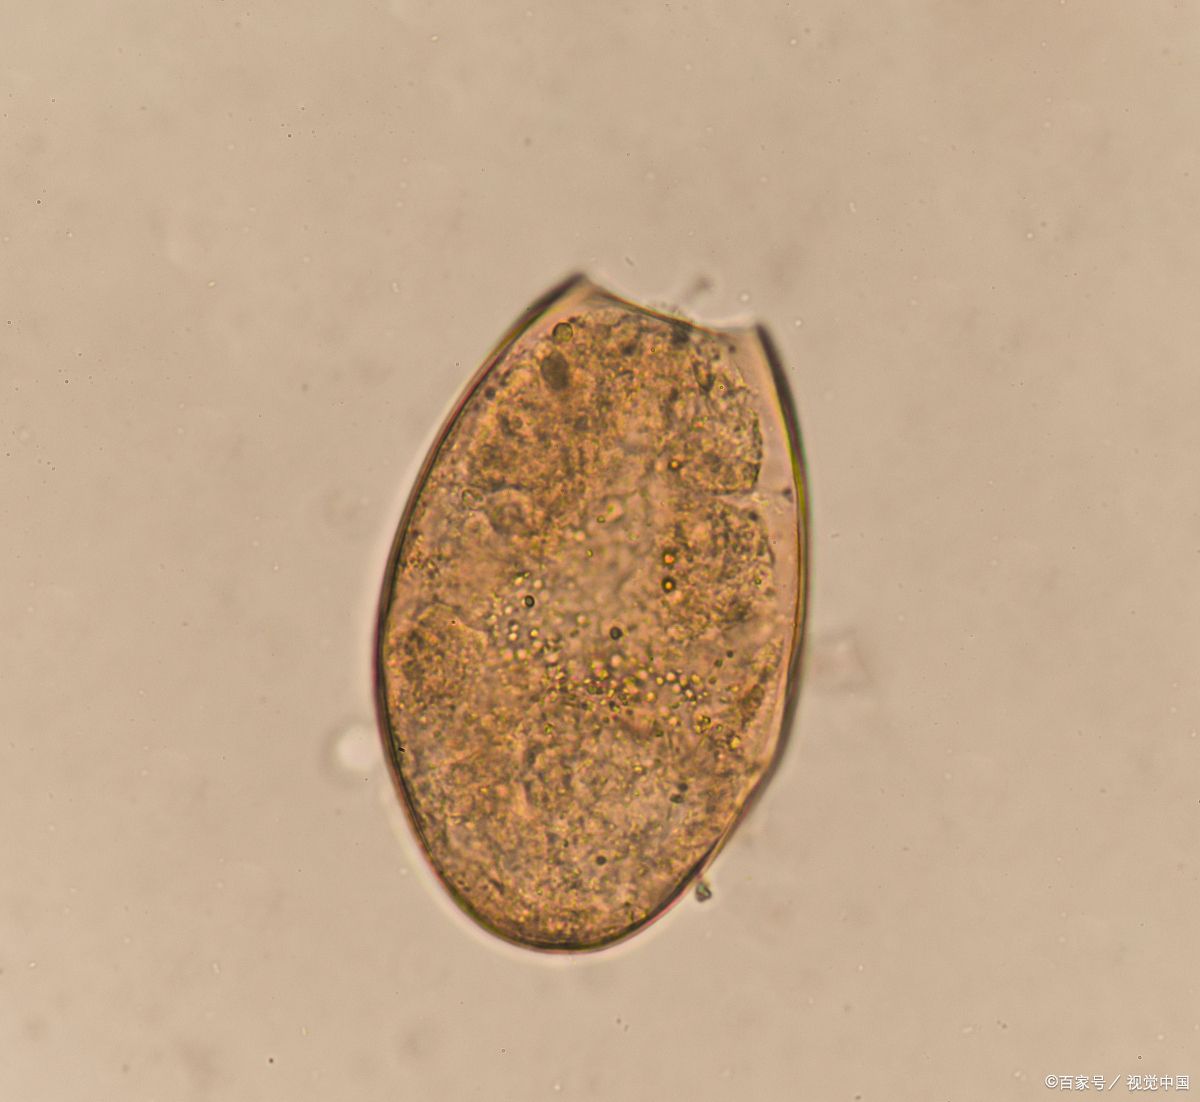

等医生取出来王先生体内这条身长3厘米的“鱼”的时候,也证实了一点:患者体内的是 肝巨片形吸虫 。

肝片吸虫病是由肝片吸虫寄生在人或动物的肝脏中引起的疾病,是我国的一种常见寄生虫病。

肝片吸虫分为两种,分别是异尖线虫和棘球绦虫。其中,异尖线虫属于囊蚴,寄生在人体或动物肝脏中;而棘球绦虫属于囊蚴,寄生在人或动物的小肠中。如果人类生吃了被污染的水生植物后,它们就进入体内小肠,长成幼虫,之后进入腹腔、肝脏。